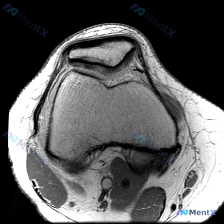

怀疑膝关节软骨异常?但单张T1WI MRI什么都没看出来,问题出在哪?

今天整理了一个很有启发意义的读片病例,问题是临床怀疑膝关节软骨异常,只给了一张矢状位T1加权MRI,我们一起来梳理整个分析过程。

这是一张膝关节矢状位T1加权像(T1WI),我们先把基础解剖评估说清楚:

- 骨骼结构:股骨远端、胫骨近端骨皮质连续,无骨质破坏或骨折,关节间隙正常,无明显骨赘增生或关节面塌陷

- 半月板:形态完整,呈均匀低信号,未见明确撕裂的高信号影

- 韧带:后交叉韧带、前交叉韧带走行连续,信号均匀无异常

- 肌腱肌肉:髌腱、周围肌肉信号均匀,无肿胀或萎缩

- 关节腔:无明显大量积液,腘窝软组织信号无异常